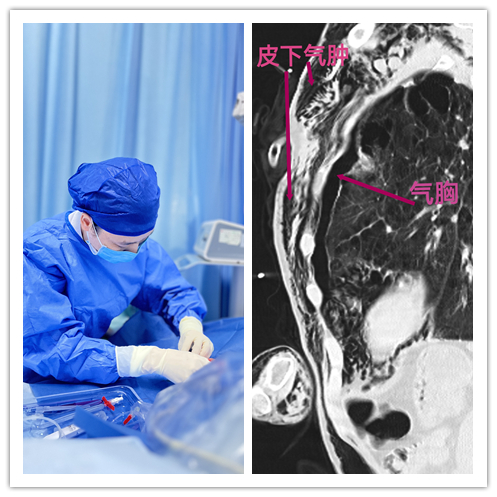

全身被气“吹肿”,超声引导为其开通生命通道

肥胖、长期输液、高度水肿、反复化疗……这些因素让一些患者的静脉血管变得脆弱而难以寻找。近日,呼吸内科三病区(呼吸ICU)为一广泛皮下气肿的患者,成功置入了经外周静脉置入中心静脉导管(PICC)。

家住安化县83岁的邹爷爷,因身患左侧大量气胸、从头到脚广泛的皮下气肿,病情危重,需要立即开通静脉通道补液抗感染治疗。然而,常规静脉穿刺无法“下手”,他的身体就像被吹胀的气球,血管踪迹难觅。因超声对气体无法穿透,所以超声引导穿刺血管遇到前所未有的挑战。管床的副主任医师曹君及其团队经过讨论后决定边排气边超声下寻找可置管的血管进行静脉穿刺。

通过静脉治疗专委会的王芬副主任护师为患者超声评估血管条件后发现,其全身都是皮下气体,无法探寻到血管。但凭借精湛的技术和丰富的临床经验,在多次赶走皮下气体再超声下探寻血管位置下,最终成功地为邹爷爷实施了PICC。像这种全身皮下气肿的患者还是非常少见,能成功置入PICC是非常不容易。”王芬表示,超声引导下静脉置管不仅提高了穿刺的成功率,更缩短了穿刺时间,为患者减轻了痛苦和焦虑,提高了操作安全性,降低了并发症风险。